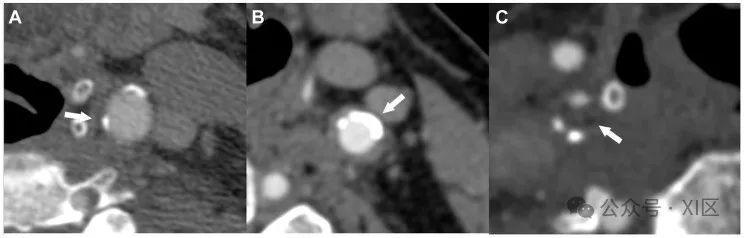

LRNC是一种异质组织,由富含脂质的巨噬细胞、胆固醇晶体、平滑肌泡沫细胞死亡以及血浆衍生脂质堆积形成,并由内膜细胞外基质大分子拴住。LRNC在动脉粥样硬化斑块的进展和易损性中起着关键作用。2017年发表的一项对16项研究的荟萃分析显示,CT血管造影显示存在低衰减斑块的患者发生同侧脑血管事件的风险几乎是其他患者的三倍,与血管狭窄程度无关。2013年发表的一项系统回顾和荟萃分析显示,LRNC可预测无症状受试者的卒中或TIA。MRI因其卓越的软组织对比度被认为是评估LRNC最敏感的方式。相反,由于IPH和LRNC的CT值明显重叠,CT扫描通常被认为灵敏度较低。同样,US检查也被认为不太适合用于区分出血和脂质成分(图3)。

图3超声(US)检查(A)和CT扫描(B、C)显示富脂质坏死核心的实例。(A)一名同侧缺血性卒中的62岁女性左侧颈总动脉非硬化性颈动脉斑块,斑块内有一个富脂坏死核心(LRNC)和厚纤维帽(FC)。(B)一名有症状的82岁男性左侧颈内动脉中的低衰减、亚闭塞斑块,其平均CT值为43 HU,类似于LRNC。(C)同侧缺血性卒中的72岁男性右侧颈内动脉中的低衰减、亚闭塞斑块,平均CT值为22 HU。然而,由于脂质和出血成分的CT值重叠,因此不能排除斑块内出血(IPH)的可能性。斑块形态